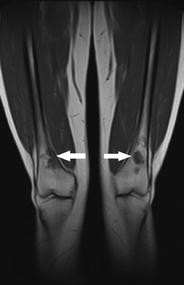

Incidental findings other than scoliosis were recorded in 104/247 (42%) patients, most often affecting the musculoskeletal system (65/247 patients, 26%). We found 16/247 (6.5%) significant incidental findings likely to affect clinical management, including avascular necrosis of bone in eight patients (five with NF2), eight insufficiency fractures, and four non-neurogenic neoplasms (Hodgkin's lymphoma, liposarcoma, dermoid cyst, large uterine myoma requiring excision). Scoliosis was seen in 50/247 patients (20%), including 8/55 with NF2 (15%) and 11/51 with schwannomatosis (22%).

Incidental findings in the neurofibromatoses frequently involve the skeleton. Given the relatively high incidence of unsuspected osteonecrosis and stress fractures, close attention to the skeleton on WBMRI is advised. In addition, knowledge of common incidental findings can help clinicians prepare patients who undergo WBMRI for potential unexpected findings.